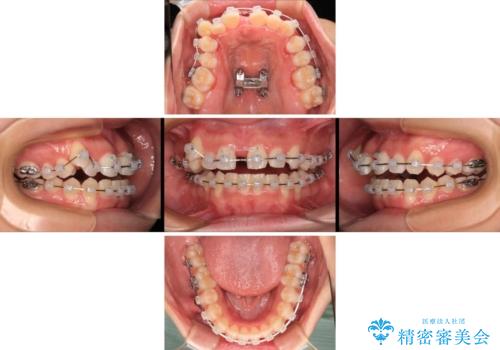

- クリアブラケット

- 上下前歯のデコボコを気にして来院された患者様です。

上顎歯列が下顎の歯列に対して狭小であり、一部下顎の奥歯が上顎よりも外側に位置している状態でした。

上顎の急速拡大装置を使用して上顎骨を側方に拡大することで上顎歯列を拡大し、下顎歯列も拡大できるようにすることで、歯列を整えることとしました。